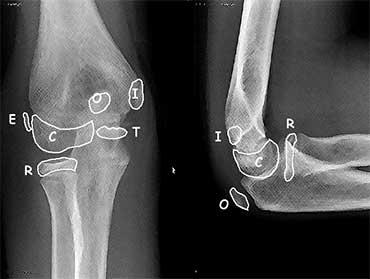

Ossification centres

Có 6 trung tâm cốt hóa xung quanh khớp khuỷu tay.

Chúng xuất hiện và hợp nhất với các xương lân cận ở các độ tuổi khác nhau.

Điều quan trọng là phải biết trình tự xuất hiện vì các trung tâm cốt hóa luôn xuất hiện theo một thứ tự nhất định.

Thứ tự xuất hiện này được xác định trong thuật nhớ C-R-I-T-O-E

(Chỏm con – Đầu trên xương quay – Mỏm trên lồi cầu trong – Ròng rọc – Mỏm khuỷu – Mỏm trên lồi cầu ngoài).

Độ tuổi mà các trung tâm cốt hóa này xuất hiện rất khác nhau và khác biệt giữa các cá nhân.

Không cần thiết phải nhớ chính xác các độ tuổi này, nhưng như một hướng dẫn chung bạn có thể ghi nhớ 1-3-5-7-9-11 tuổi.

The Ròng rọc (Trochlea) có hai hoặc nhiều trung tâm cốt hóa, có thể tạo ra hình ảnh ròng rọc bị phân mảnh.

Trên hình chiếu bên, các điểm cốt hóa ròng rọc có thể chiếu vào trong khớp.

Không nên nhầm lẫn chúng với các dị vật tự do trong khớp (mũi tên).